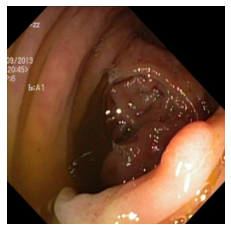

(a) Refer to caption Refer to caption Refer to caption Refer to caption Refer to caption Refer to caption

(b) Refer to caption Refer to caption Refer to caption Refer to caption Refer to caption Refer to caption

(c) Refer to caption Refer to caption Refer to caption Refer to caption Refer to caption Refer to caption

(d) Refer to caption Refer to caption Refer to caption Refer to caption Refer to caption Refer to caption

(e) Refer to caption Refer to caption Refer to caption Refer to caption Refer to caption Refer to caption

(f) Refer to caption Refer to caption Refer to caption Refer to caption Refer to caption Refer to caption

(g) Refer to caption Refer to caption Refer to caption Refer to caption Refer to caption Refer to caption

(h) Refer to caption Refer to caption Refer to caption Refer to caption Refer to caption Refer to caption

Figure 3: Sample data used and generated in the different steps of PolypConnect pipeline. (a) - real polyp images, (b) - manually annotated polyp masks, (c) - randomly selected colon images used as input to the final step of PolypConnect, (d) - extracted edge images of row c. (e) - extracted edge images of polyp regions of row a using the masks of row b. (f) - combined edge images of row d and f. (g) - generated polyp on the images of row c using EdgeConnect. (h) - generated samples from AOTGAN.